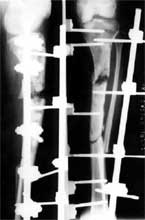

股骨远段骨折,4次钢板固定均失败,改用带锁髓内钉固定,7个月后骨折愈合。